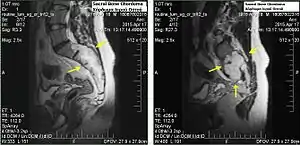

Chordomas can arise from bone in the skull base and anywhere along the spine. The two most common locations are cranially at the clivus and in the sacrum at the bottom of the spine.[2]

Sacral chordoma is presented with chronic low back pain.[3]